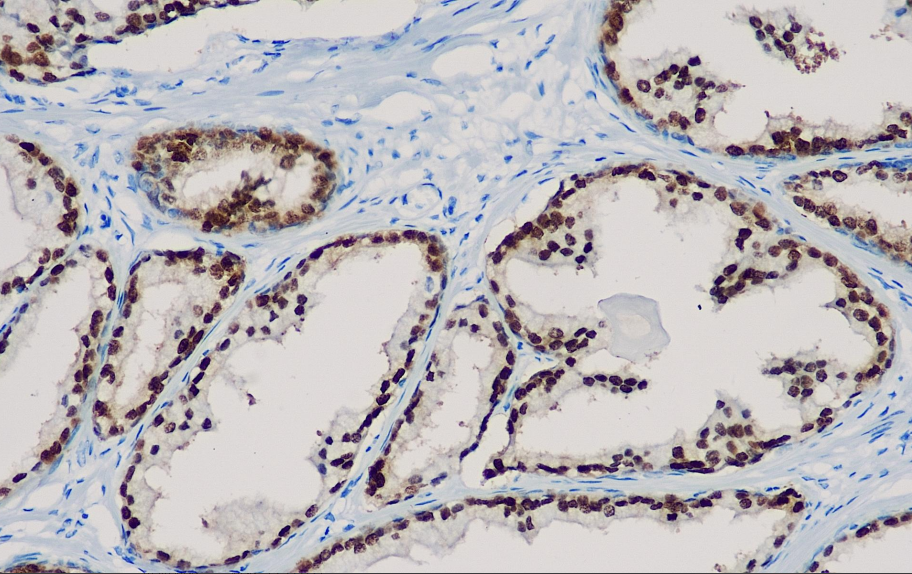

Cellular localization: nucleus

Positive control: Prostate

NKX3.1 is a prostate-specific androgen regulatory homeobox gene located on chromosome 8p. High-grade prostate cancer and high-grade urothelial carcinoma samples stained with HE are difficult to distinguish. Currently, prostate cancer markers such as PSA and PSAP can effectively determine whether prostate cancer originates from the prostate or other locations, but they have relatively low sensitivity in differentiating poorly differentiated or well-differentiated cases. NKX3.1 is a sensitive and specific tissue marker that can distinguish prostate cancer from urothelial carcinoma. At present, thrombomodulin and uroplakin are used to identify tumors of urothelial origin, but their sensitivity is not good. NKX3.1 is a sensitive and specific tissue marker for prostate cancer, which can be used to distinguish prostate cancer, urothelial carcinoma and unknown primary lesions.

The NKX3.1 antibody reagent can specifically bind to the NKX3.1 molecular antigen. The immunohistochemical kit containing the NKX3.1 antibody reagent is suitable for the precise diagnosis of prostate cancer.